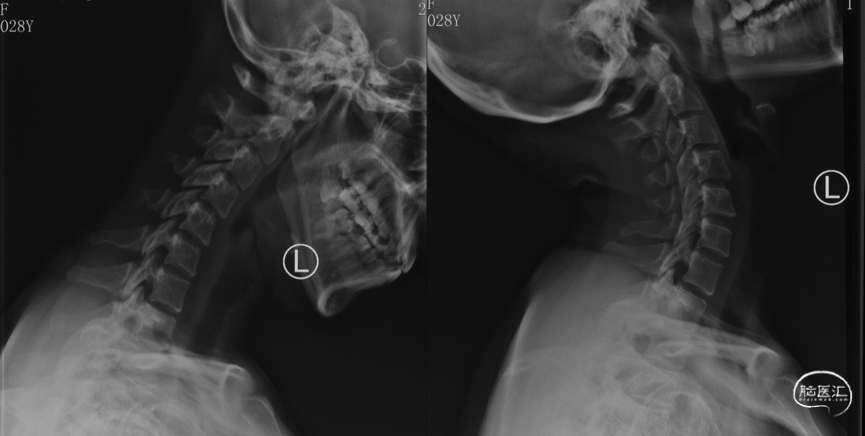

颈椎前屈后伸位X线

X线显示无颈椎不稳定,为半坐位必需的检查。